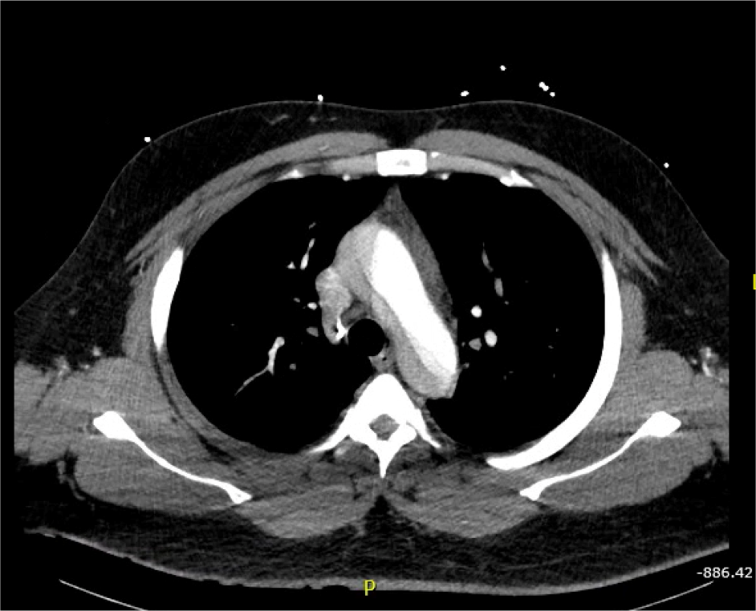

Patient’s initial EKG showed ST elevation in anterior leads, with possible ST depression in inferior leads, and T wave inversion in lateral leads. Given the patient’s clinical presentation and appearance, there was concern for ongoing ischemia. Based on the patient’s history of pain radiating into the abdomen and severe hypertension, there was additional concern for aortic dissection. This led to the cancelation of the catheterization lab activation. Slices of his computed tomography (CT) scan are shown below, revealing a severe type A aortic dissection, dissecting from the coronary arteries to the bilateral iliac arteries. Patient was started on nitroprusside and esmolol infusion and transferred emergently for cardiovascular surgery. He was discharged from the hospital in good condition less than one week later following an uncomplicated post-operative course.